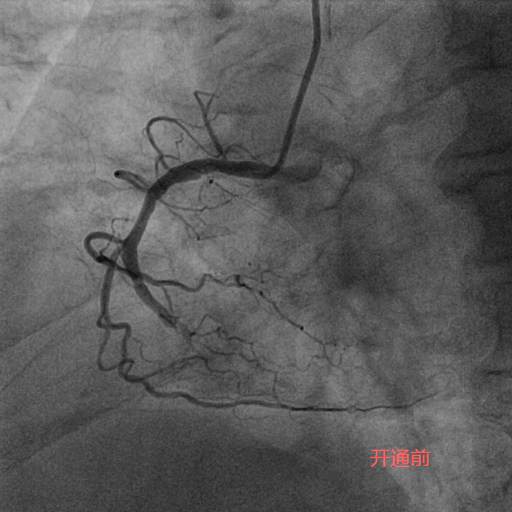

今年83岁高龄的刘老先生,退休前从事地质工作,平素身体硬朗,但近期发现快走后出现憋气症状,到某医院就诊,冠状动脉造影检查为三支病变,前降支(LAD)、回旋支(LCX)、右冠状动脉(RCA)均为完全闭塞病变且伴重度钙化。在经过近一个小时的尝试后,闭塞血管未开通,建议药物治疗。但药物治疗并未缓解刘老先生的症状,心功能反而一步步下降。后来患者及家属抱着极大的期望去某著名心脏专科医院就诊,经过半个小时的尝试后开通失败,并告知患者家属这样的血管不可能开通,冠状动脉搭桥术是唯一的出路。但是搭桥手术对于一位83岁高龄的老人来说无疑是一个艰难巨大的挑战。两次失败手术的打击使得刘老先生的身体状态每况愈下,稍事活动就气喘吁吁,逐渐对生活失去了信心。后来家属辗转打听到北京潞河医院心内科翟光耀主任团队致力于冠状动脉复杂手术,抱着最后一搏的想法,在经过两个月的药物调整后能耐受再次手术的前提下,刘老先生再次躺在了手术台上。术中,冠状动脉造影结果让翟光耀主任团队意识到了这次手术的难度之大,风险之高。三支主干闭塞,之前手术开通失败已造成血管近端夹层,闭塞的血管(尤其是RCA)全程重度钙化,近乎全程闭塞,开通血管无疑在花岗岩上开凿隧道。在经过近4个小时的不懈努力,团队终于成功开通了难度最大的RCA并植入支架,观察一天后顺利出院。 一个月后,刘老先生闭塞的LAD也成功开通。现在,刘老先生身体恢复良好,如获新生!

李奶奶今年92岁高龄,两年前曾因“急性心肌梗死”就诊于某医院,接诊专家考虑患者年龄大,合并症多,冠状动脉介入操作风险高,建议药物治疗。近半个月,李奶奶的胸痛症状频繁发作,药物治疗效果不佳,经过病友的介绍,家属选择了潞河医院翟光耀主任团队。在心脏监护室医护人员的精心治疗和护理下,李奶奶心功能改善,肺部感染得到控制,可以耐受手术。术中,冠状动脉造影显示LAD弥漫重度狭窄,RCA完全闭塞伴重度钙化。在经过近两个小时的不断尝试及努力后,闭塞的RCA成功开通,“介入无植入”未植入支架,血管成功修复。术后李奶奶恢复良好,顺利出院。